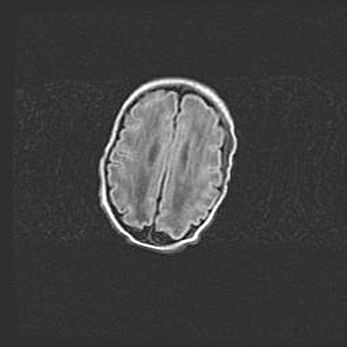

Лейкомаляция с кистозно-глиозной дегенерацией головного мозга.

Возраст: 2 месяца 25 дней

Вес: 6400 г

Окружность головы: 40 см

Срок гестации: 41 неделя

Лейкомаляцию относят к ишемически-гипоксическим повреждениям головного мозга, диагностируемым у новорожденных. При лейкомаляции в головном мозге обнаруживают очаги некроза, возникшие после тяжелой гипоксии и нарушения кровотока. В процессе морфогенеза очаги проходят три стадии: 1) развития некроза, 2) резорбции и 3) формирования глиозного рубца или кисты. Перивентрикулярная лейкомаляция (ПЛ) встречается примерно в 12% случаев среди новорожденных, обычно – у недоношенных детей, причем, частота ее зависит от массы, с которой младенец появился на свет. Наибольшее число малышей страдает лейкомаляцией, если масса при рождении 1500-2500 г.